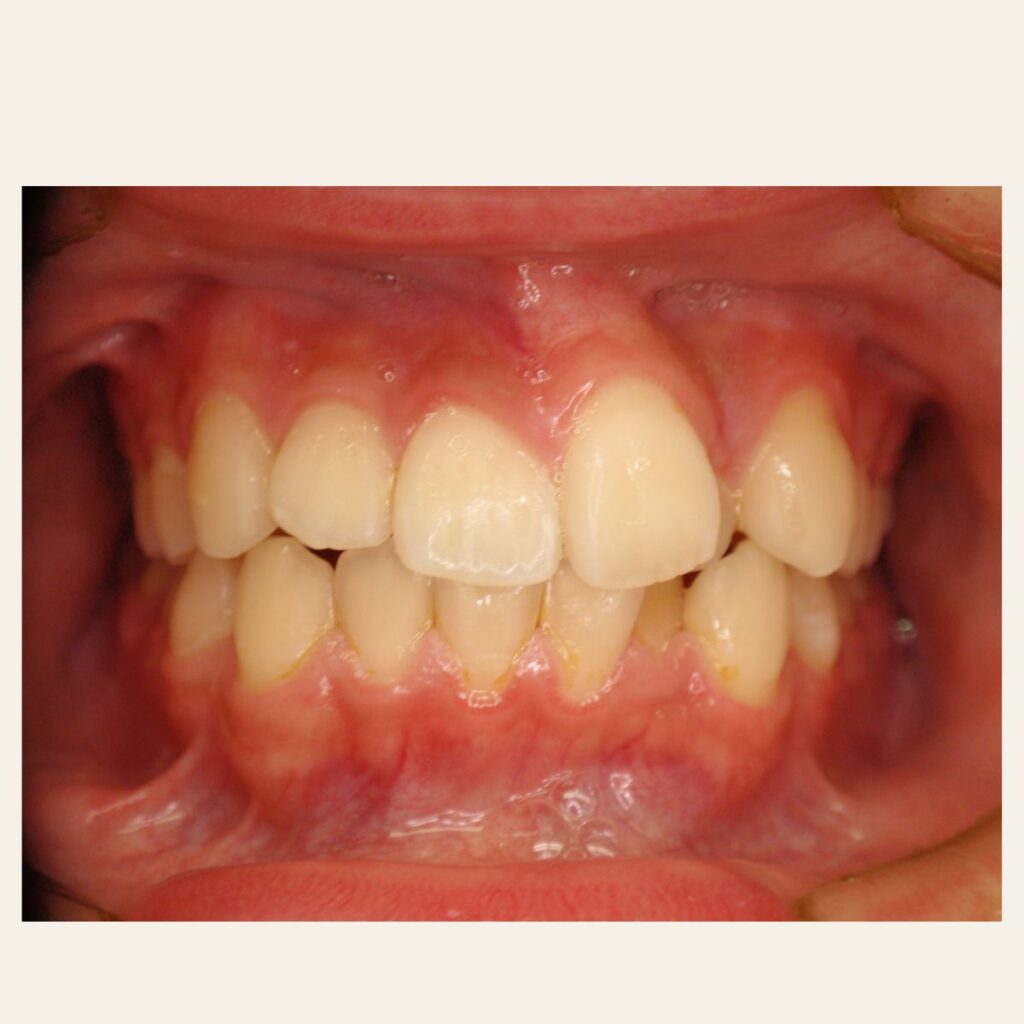

叢生の症例1(表側矯正)

治療前後(BEFORE/AFTER)

| 年齢 | 10代男性 |

| 主訴 | 前歯のガタガタ |

| 診断 | 叢生 |

| 治療方法 | 上下・表側ワイヤー矯正(今回抜歯はしていません) |

| 治療期間 | 11か月 |

| 費用 | 1,050,500円(税込) |

| リスク・副作用 | 痛み/歯根吸収/歯肉退縮/後戻り など |

本症例では歯が重なっている叢生と、前から見ると曲がっている状態でした。

歯列のスペースを確保しながら歯並びを整えるため、

表側矯正を用いて治療を行いました。

治療後は歯並びとかみ合わせが改善し、

見た目だけでなく歯磨きもしやすい状態になりました。

※虫歯の治療は矯正治療後に仕上げています。

※正中を合わせるには抜歯等が必要になる場合があります。